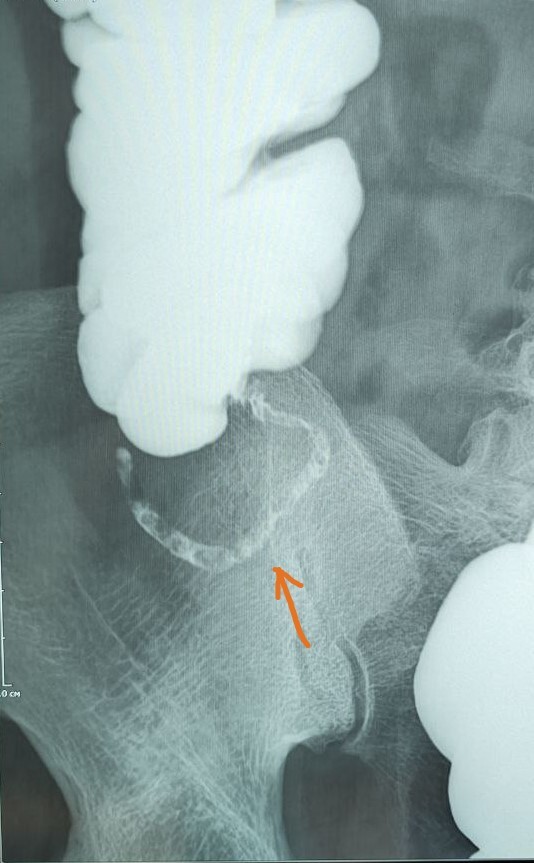

Р-скопия желудка стоя

Описание: на рентгеноскопии желудка положении Тренделенбурга -над диафрагмой находится мешковидно расширенный брюшной сегмент пищевода, кардия расположена на уровне диафрагмы. Заключение: ГПОД 1ст

По 565 постановлению, I ст. ГПОД- над диафрагмой находится брюшной сегмент пищевода, кардия расположена на уровне диафрагмы.